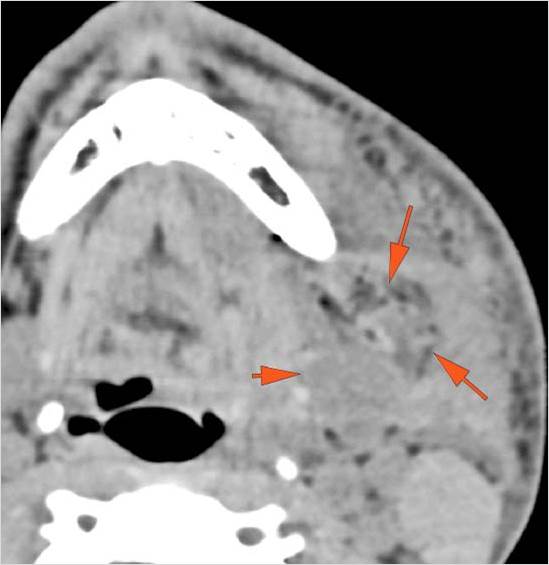

There is localized edema, hematoma or abscess within in the periauricular, other facial or scalp soft tissues, SMAS, infratemporal fossa, masticator space or oral cavity. [Yes/No]

There is evidence of gas or a foreign body at a possible fracture site, indicative of an open or penetrating injury. [Yes/No]

There is soft tissue swelling suggesting injury to the parotid or submandibular glands. [Yes/No]